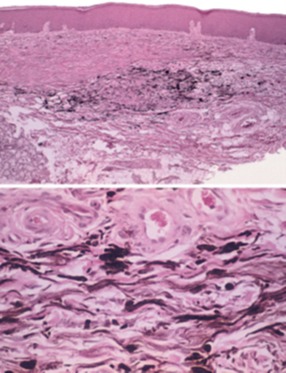

24.45歲男性因下唇黑色斑塊求診,臨床所見如附圖一,切片檢查如附圖二,其正確診斷為下列何者?

melanotic macule: increased melanin pigmentation distributed along basal epithelial layer. 排列整齊

Blue nevus: spindle-shaped melanocytes located relatively deep within the lamina

propria and parallel to the surface epithelium.